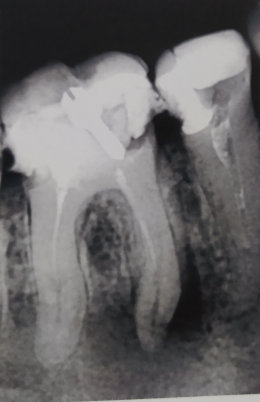

После удаления нерва из зуба, кажется четырнадцатый, на верхней челюсти, проткнули на 2 сантиметра дальше корня, я показался другому врачу и он говорит, что теперь нужно удалять зуб.

Неужели ничего нельзя поделать, чтобы сохранить зуб? Чем-то запломбировать этот канал? Мне 66 лет, их, зубов, уже почти не осталось.

В принципе, доктор прав, также возможно провести хирургическую манипуляцию (резекция верхушки корня).